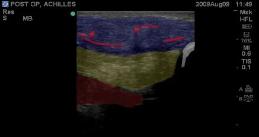

Post-operative Achilles Tendon